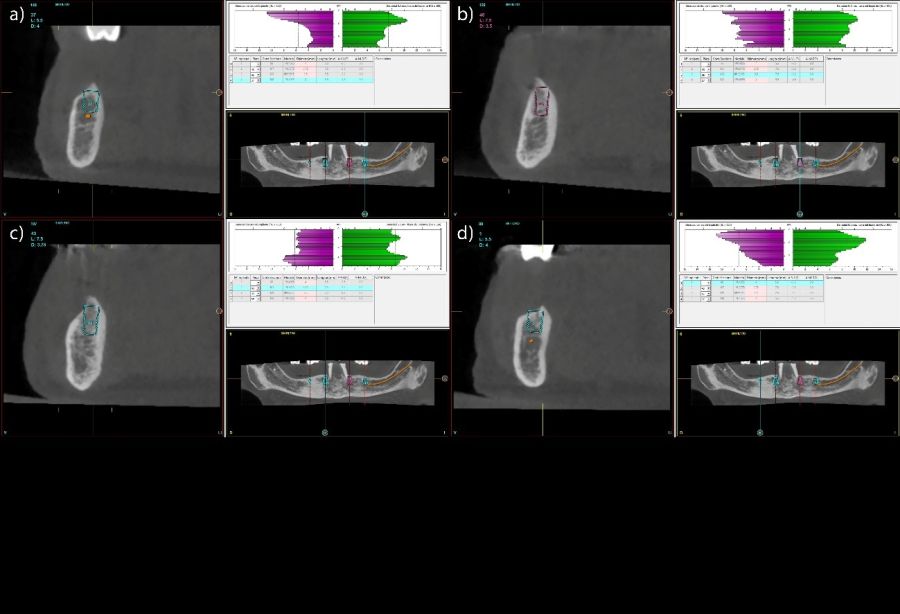

Se llevó a cabo un estudio retrospectivo sobre una cohorte consecutiva de pacientes rehabilitados mediante prótesis híbridas mandibulares soportadas por cuatro implantes. Los tratamientos fueron realizados en un centro privado especializado en implantología oral (Vitoria, España) durante los años 2001-2018. Solo se incluyeron en el análisis aquellos pacientes que hubieran completado de forma íntegra el seguimiento clínico y radiográfico hasta la fecha actual, lo que garantizó la disponibilidad de registros comparables a lo largo de todo el periodo de observación. Todos los pacientes presentaban mandíbulas completamente edéntulas rehabilitadas mediante cuatro implantes, existiendo dos grupos: 4 implantes largos interforaminales sin angulación y 4 implantes cortos distribuidos en la mandíbula totalmente edéntula de forma biomecánicamente favorable. La intervención quirúrgica fue llevada a cabo por el mismo profesional siguiendo el protocolo de fresado biológico46, que se caracteriza por trabajar a bajas revoluciones y sin irrigación externa, favoreciendo la preservación del hueso autólogo y optimizando la estabilidad primaria del implante. Durante la inserción se registró el torque final alcanzado y se documentaron las características anatómicas del lecho mediante el Cone-Beam Computed Tomography (CBCT) preoperatorio, a partir del cual se obtuvieron los valores de densidad ósea expresados en unidades Hounsfield (HU). Los implantes se clasificaron posteriormente en dos grupos según su longitud: cortos (<10 mm) y largos (≥10 mm).

Todas las rehabilitaciones protésicas siguieron un mismo protocolo estandarizado. Una vez completada la cirugía, se procedió a la carga inmediata mediante una prótesis provisional atornillada sobre pilares transepiteliales, diseñada para distribuir las cargas de forma progresiva durante los primeros meses. Pasado un intervalo de entre seis y doce meses, y tras confirmar la estabilidad clínica y radiográfica de los implantes, se elaboró la prótesis definitiva. Esta consistió en una estructura metálica, revestida con resina acrílica, conformando una prótesis híbrida atornillada que mantenía el mismo esquema funcional que la provisional. El control radiográfico se llevó a cabo mediante radiografías panorámicas estandarizadas, realizadas siempre con el mismo sistema de posicionamiento reproducible, que incluía referencias en el suelo para los pies y apoyos simultáneos en glabela y mentón, con el fin de mantener constantes las relaciones angulares y minimizar la distorsión entre visitas. La medición de la pérdida ósea marginal se efectuó sobre la última radiografía panorámica obtenida bajo este protocolo de estandarización. Una vez digitalizada la imagen, se procedió a su calibración mediante un software específico (Digora for Windows, SOREDEX Digital Imaging Systems), utilizando como referencia una longitud conocida (el propio implante). Tras incorporar dicho valor, el programa corregía la magnificación inherente de la técnica panorámica, permitiendo realizar mediciones lineales exactas y exentas de distorsión. La pérdida ósea marginal se cuantificó en las superficies mesial y distal de cada implante, expresándose siempre como valor absoluto.

Fueron evaluadas 26 prótesis híbridas mandibulares soportadas por cuatro implantes, lo que genera un total de 104 implantes. De estas 26 prótesis, 12 fueron prótesis sobre implantes cortos (longitud < 10 mm) y 14 como prótesis sobre implantes largos (≥ 10 mm). La muestra presentó un claro predominio femenino, con 21 mujeres (80,8%) y 5 varones (19,2%). La edad media de los pacientes fue de 69,7 ± 11,2 años en el momento del inicio del estudio. A nivel de implante, la densidad media del hueso receptor fue de 866.16 ± 146.35 HU, mientras que el torque medio de inserción alcanzó 47.88 ± 9.01 Ncm. En cuanto a los diámetros de los implantes, en el grupo de los implantes cortos, el más frecuente fue el de 3,5 mm con un 56,5% de los casos, mientras que en el grupo de los implantes largos el diámetro predominante fue para 3,5 y 3,75 mm con un 32,1% para cada una de las categorías (Figura 1.a). En cuanto a la distribución de las longitudes, en el grupo de los implantes cortos, la más frecuente fue 7,5 mm con un 54,3% mientras que en los implantes largos la más frecuente fue 10 mm (47,2%) (Figura 1.b).

Todos los implantes fueron rehabilitados con prótesis híbridas atornilladas, sobre transepitelial. Este transepitelial presentó una altura entre 1 y 4 mm siendo el más frecuente 3 mm en el 75,8% de los casos. La distribución de las alturas de los transepiteliales se muestra en la Figura 2.

El análisis global de los 99 implantes reveló una pérdida ósea marginal media de 0,77 ± 0,26 mm en la superficie mesial y 0,79 ± 0,29 mm en la distal, valores que se mantuvieron dentro de los rangos considerados clínicamente aceptables para rehabilitaciones mandibulares. Cuando los implantes se categorizaron según su longitud, se observaron diferencias claras entre ambos grupos. Los implantes cortos (<10 mm) mostraron una pérdida ósea mesial media de 0,61 ± 0,23 mm y distal de 0,56 ± 0,22 mm, mientras que los implantes largos (≥10 mm) presentaron pérdidas significativamente mayores (mesial: 0,92 ± 0,19 mm; distal: 0,99 ± 0,17 mm). Dado que las pruebas de normalidad (Shapiro–Wilk) mostraron una distribución no normal en todos los grupos (p < 0,001), se aplicó la prueba no paramétrica de Mann–Whitney U. Los resultados confirmaron diferencias estadísticamente significativas tanto en la pérdida ósea mesial (U = 2068,5; p < 0,001) como en la distal (U = 2247,0; p < 0,005), indicando que los implantes cortos presentaron un comportamiento óseo más favorable que los implantes largos a lo largo del tiempo. Durante el tiempo de seguimiento que fue de media de 12,2 años (+/- 4,4; rango 6-23 años) no se objetivaron fracasos en ninguno de los implantes por lo que la supervivencia acumulada fue del 100%. El análisis del periodo de seguimiento mostró diferencias claras entre ambos grupos. Los implantes largos (≥10 mm) presentaron un tiempo medio de función de 14,1 ± 4,2 años (rango: 9–23 años), mientras que los implantes cortos (<10 mm) registraron un seguimiento significativamente menor, con una media de 9,8 ± 2,7 años (rango: 6–15 años). En las Figuras 3- 10 se muestran dos casos incluidos en el estudio, uno de cada situación descrita.